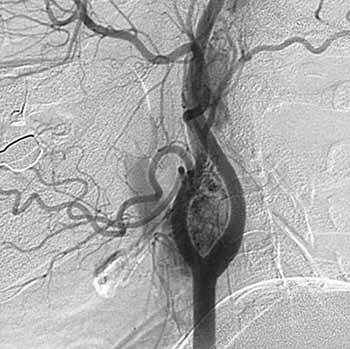

Рис. 4. Ангиограмма. Множественные параганглиомы.